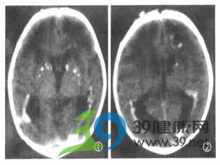

钙化影简介:钙化影一般都是由于机体组织受损后,机化,钙盐沉积形成的。形成原因很多。一般来说,肺部的钙化影有可能表示你曾经得过肺结核,但是病灶局限住了。其他部位的也可能是结核。而如果在胆道系统,泌尿系统里的钙化影很可能是结石。循环系统的钙化影可能是老年性的退行性钙化病变。

钙化影一般都是由于机体组织受损后,机化,钙盐沉积形成的。形成原因很多。一般来说,肺部的钙化影有可能表示你曾经得过肺结核,但是病灶局限住了。其他部位的也可能是结核。而如果在胆道系统,泌尿系统里的钙化影很可能是结石。循环系统的钙化影可能是老年性的退行性钙化病变。

- 5、 基底核钙化症,可能伴随智能减退、强迫行为、神志淡漠等症状,应去神经内科就诊。